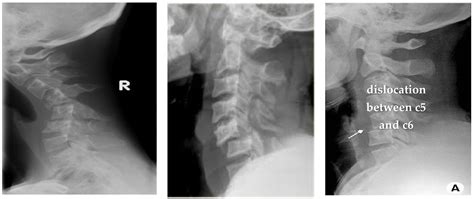

• cervical dislocation symptoms

• cervical vertebrae dislocation

• cervical dislocation definition